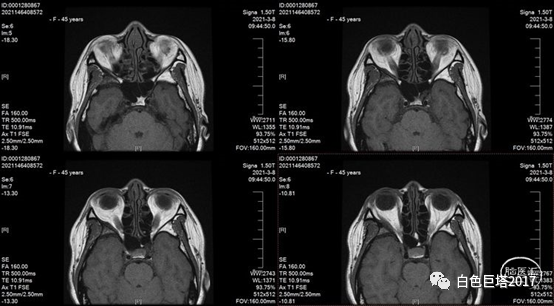

患者1年余前无诱因感右眼肿胀,无外伤病史,无头晕、头痛,无发热,无视力下降,无眼球搏动、杂音。因右眼肿胀进展曾于2020-12-10在我院眼科门诊就诊,行眼眶MRI平扫示:右上眼睑水肿样改变;右侧蝶骨大翼异常骨质改变伴内侧缘异常软组织性质待定。2020-04-16患者感右侧眼球突出肿胀仍进展,来院就诊。

外院曾行磁共振+增强检查提示右侧蝶骨大翼异常信号,考虑骨纤维异常增殖,未考虑肿瘤。

下图红箭头示磁共振增强提示局部脑膜强化